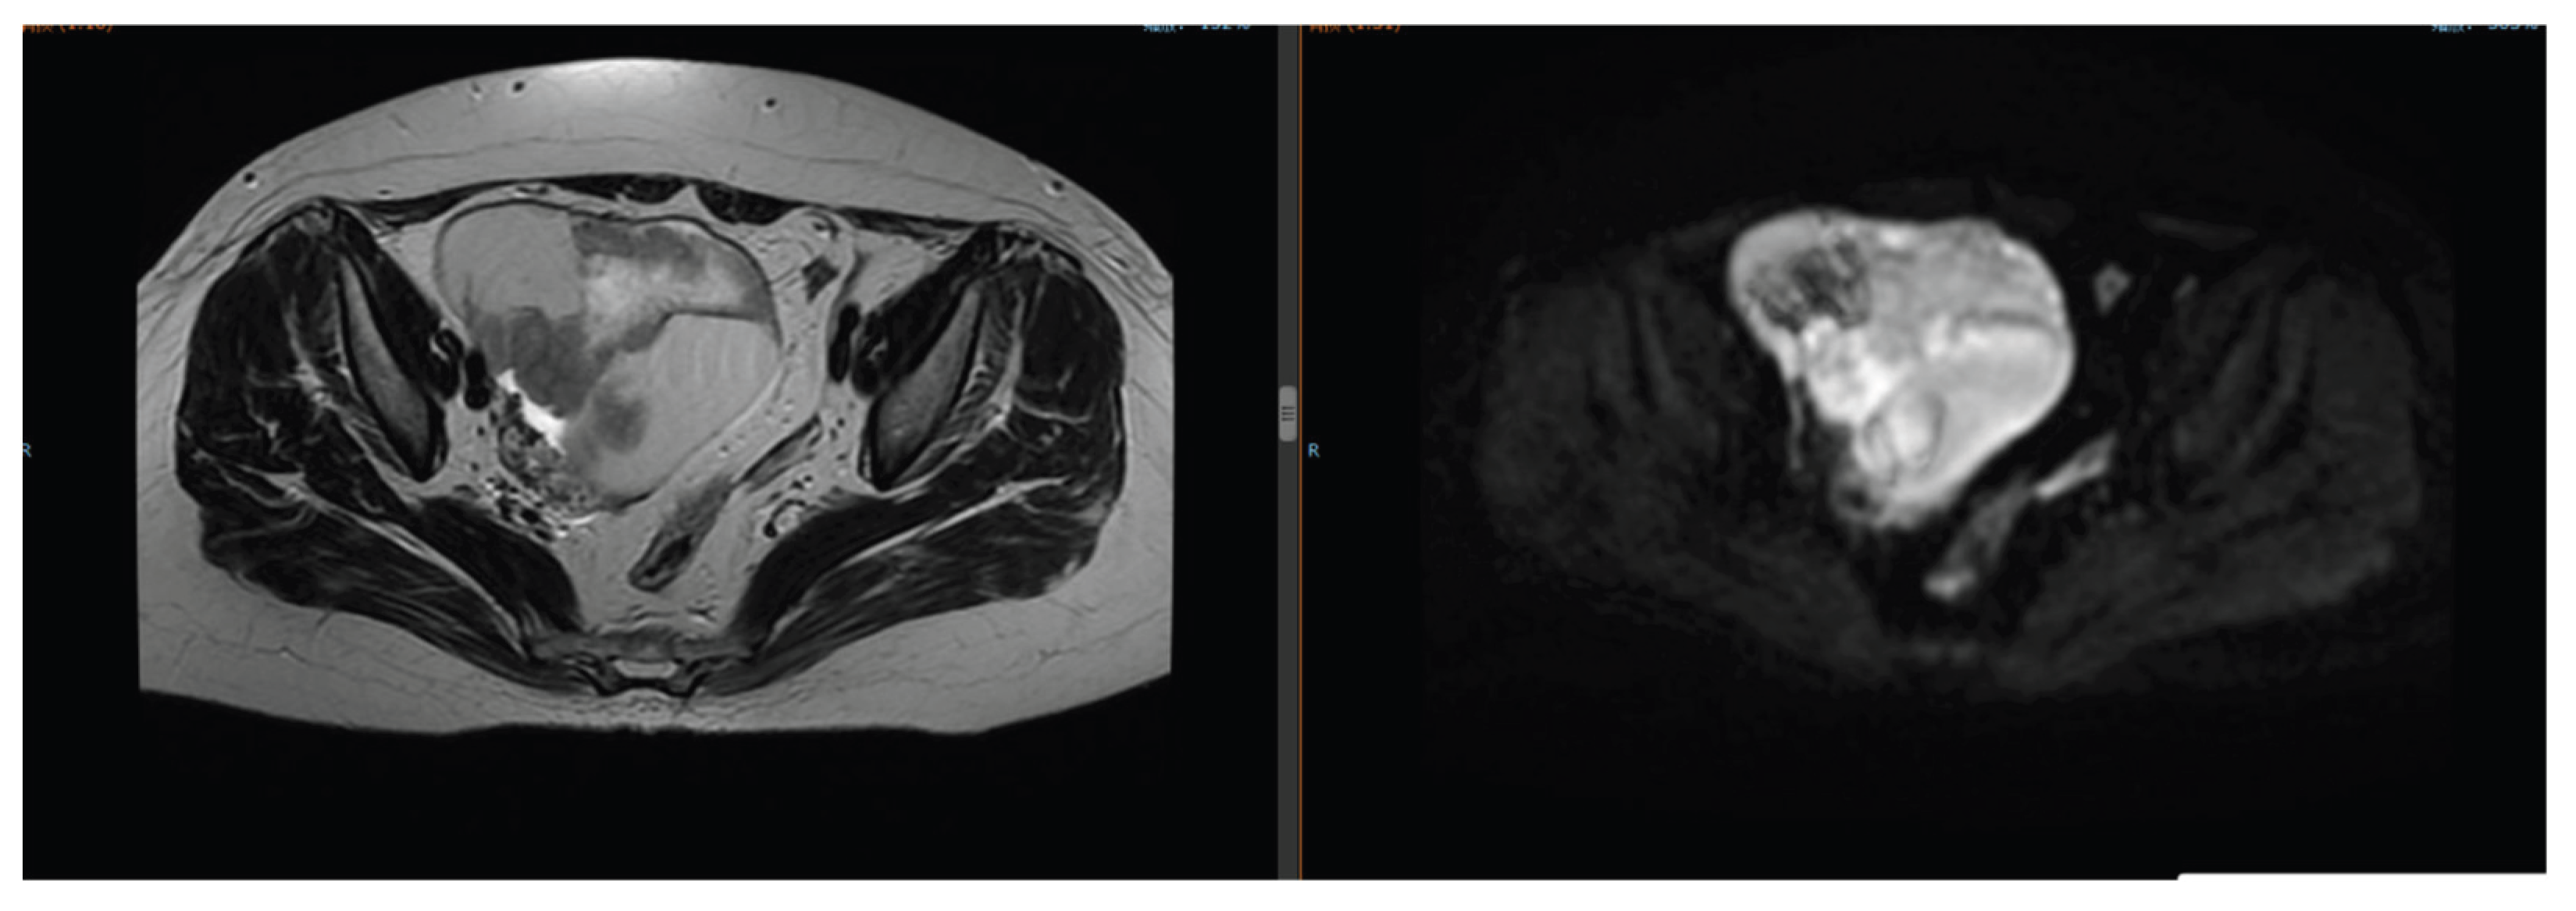

The patient developed lower abdominal distension and pain. Pelvic magnetic resonance imaging (MRI) revealed a left ovarian mass (6.8 cm × 5.2 cm) (Figure 7). Needle biopsy confirmed an ovarian epithelial-derived tumor, morphologically consistent with endometrioid carcinoma. Immunohistochemistry results: PAX-8 (+), ER (strong +, 90%), PR (strong +, 80%), TTF-1 (-), Napsin A (-), Ki-67 (+, ~40%) (Figure 8). She was diagnosed with primary ovarian cancer (FIGO Stage Ⅲ), excluding lung metastasis due to significant differences in pathological type and immunophenotype from lung adenocarcinoma.

Figure 7. Pelvic MRI on August 29, 2024: Left ovarian mass (6.8 cm × 5.2 cm).